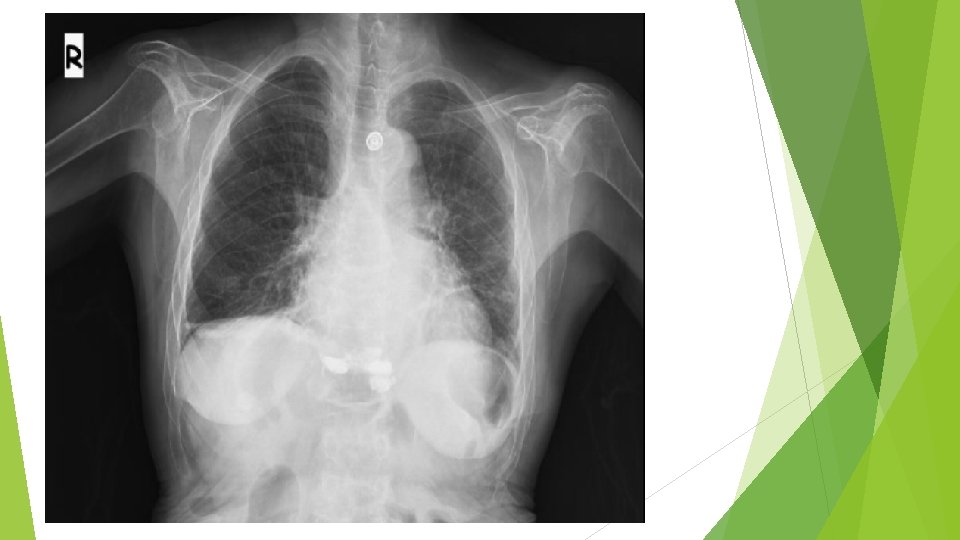

Endokrinoloji: hipoglisemisi olan , tansiyon 90/60 olan, ra nedeniyle almakta olduğu prednolü 3 gündür almadığı öğrenilen hasta endokrinoloji adına uzm dr sinem kargün e danışıldı adrenal yetmezlik? prednol 20 mg iv puşe yapılması kontrol kan gazı görülmesi kontrol kan şekeri görülmesi nefroloji önerisine uygun iv hidrasyon devam edilmesi crp 22 nötrofilik lökositoz olan immünsüpresıf hastanın olası enfeksiyoz odaklardan acısından pa akciğer grafisi çekilmesi, olası enfeksiyoz odak açısından enfeksiyon hastalıkları görüşü alınması